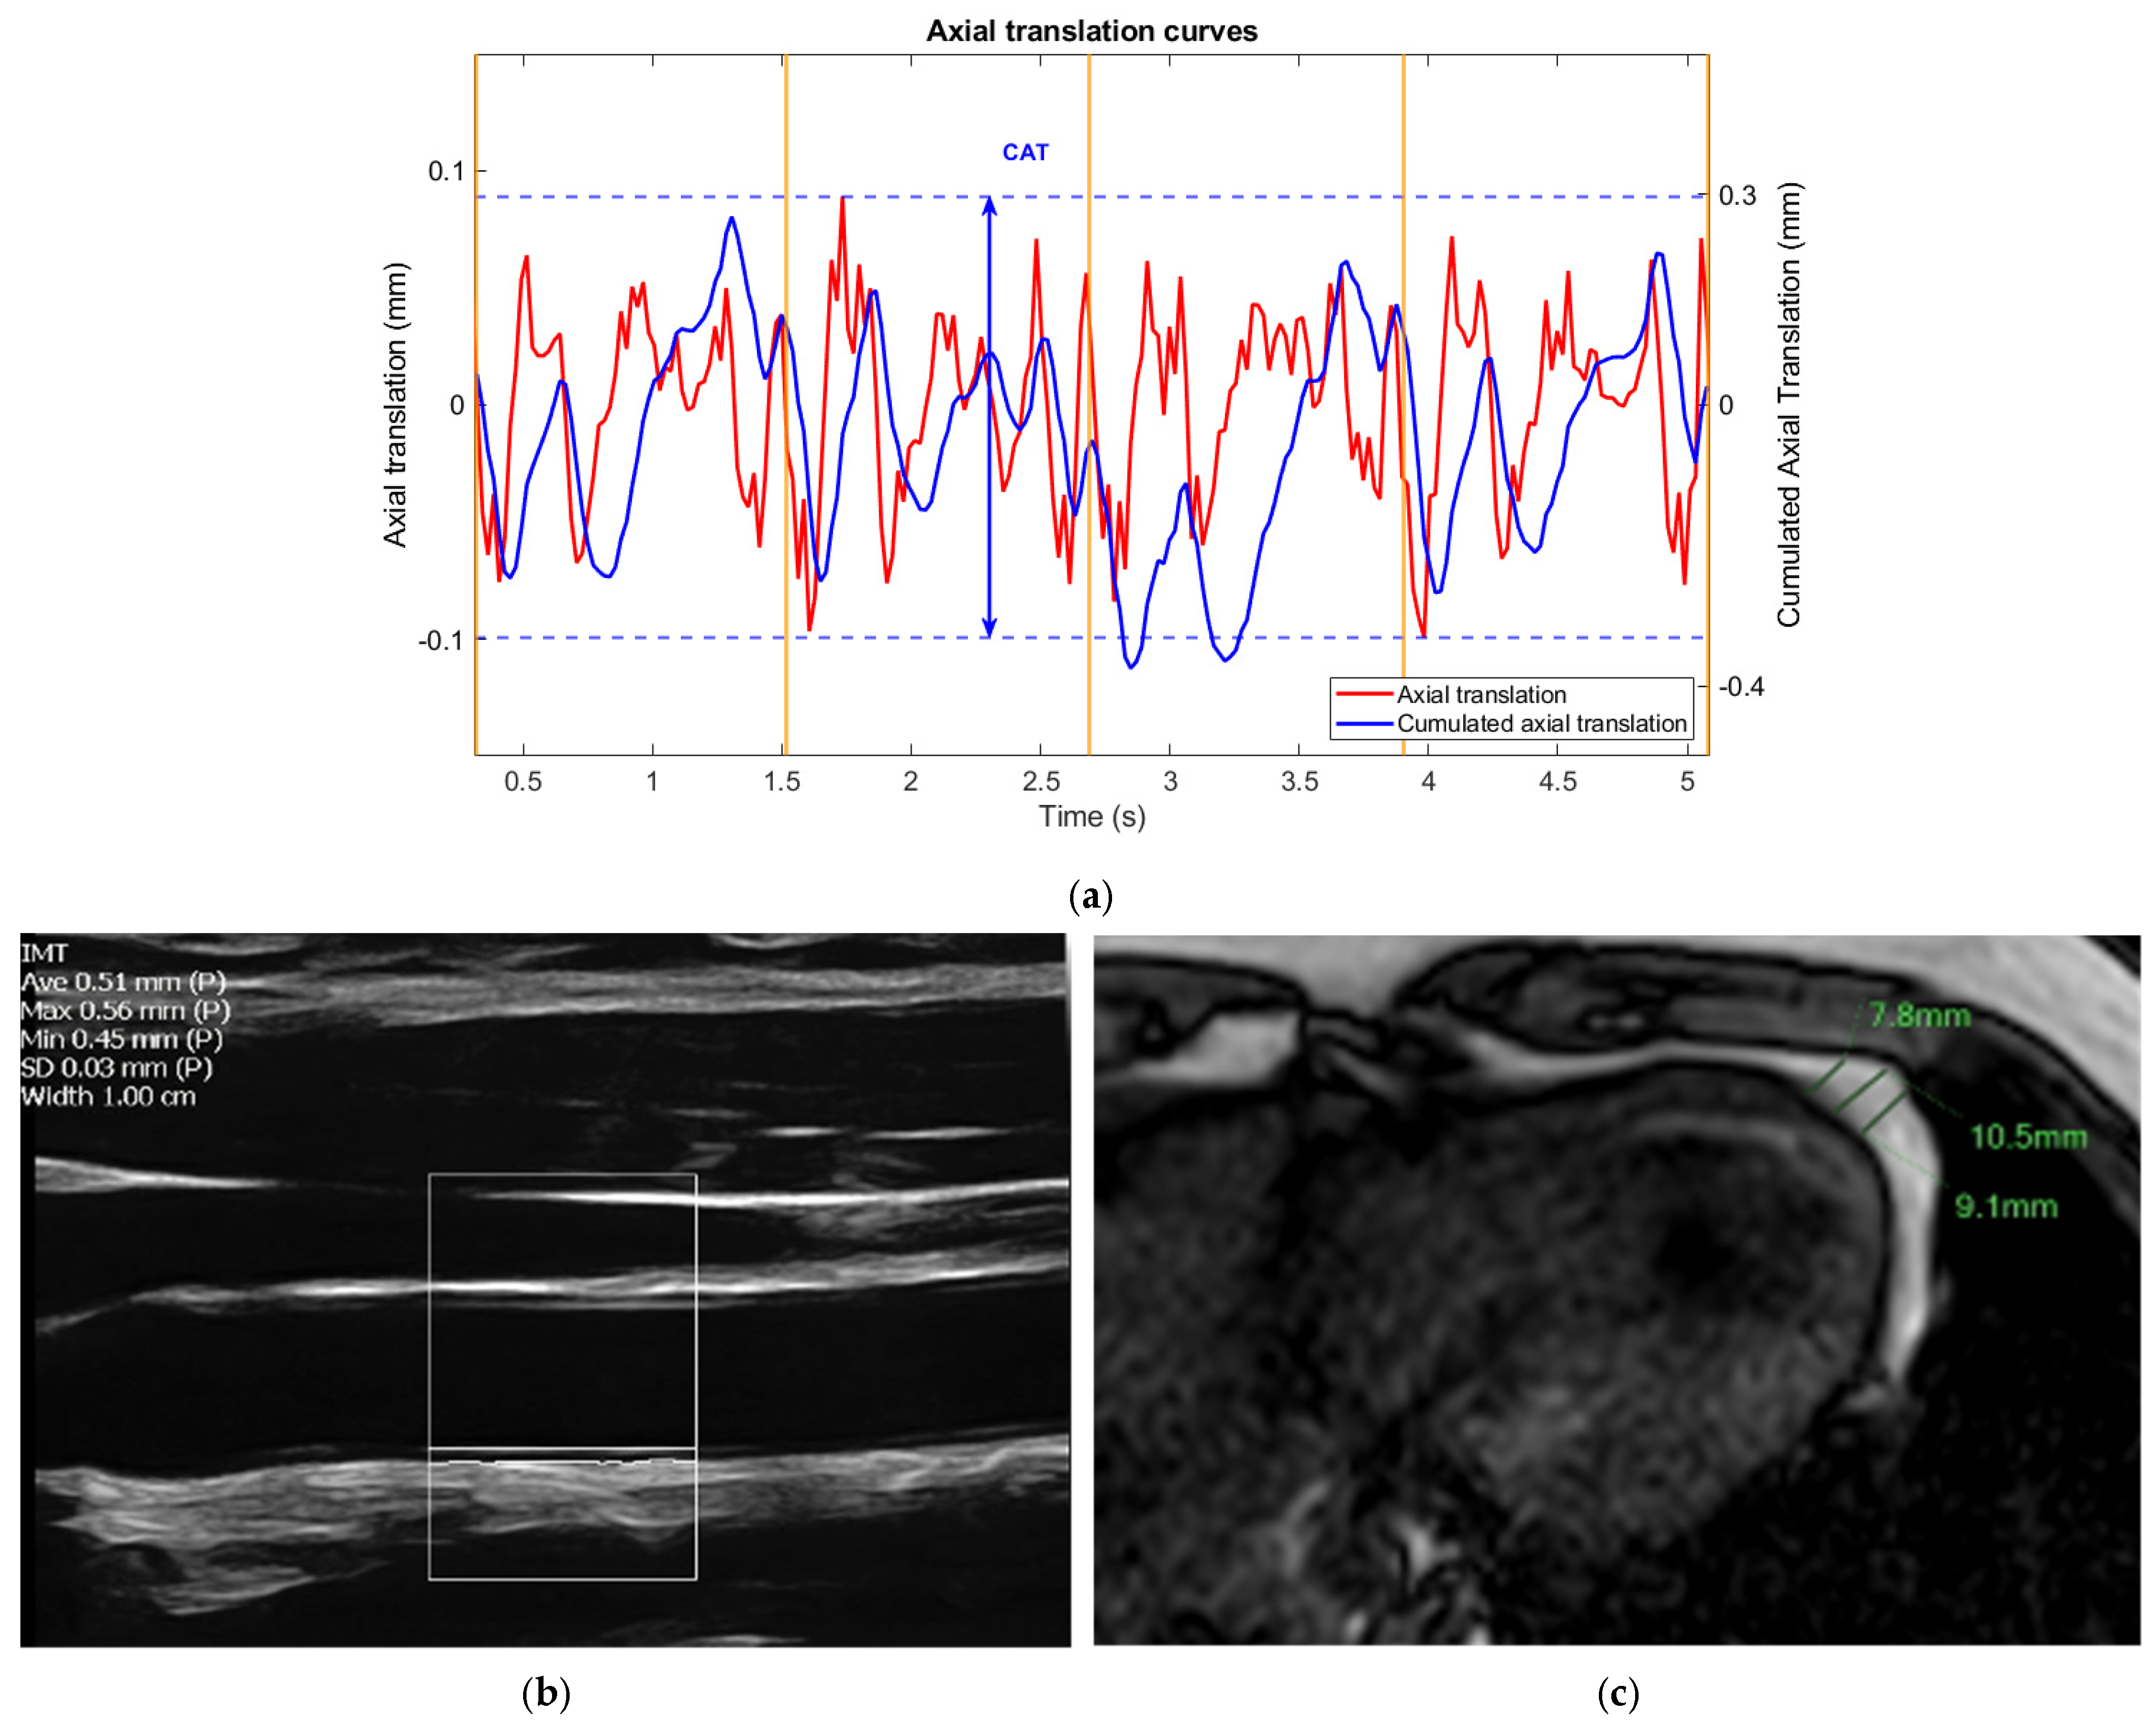

- Carotid ultrasound

- Non-Invasive Vascular Elastography (NIVE)

- Measurement of pericardial fat thickness